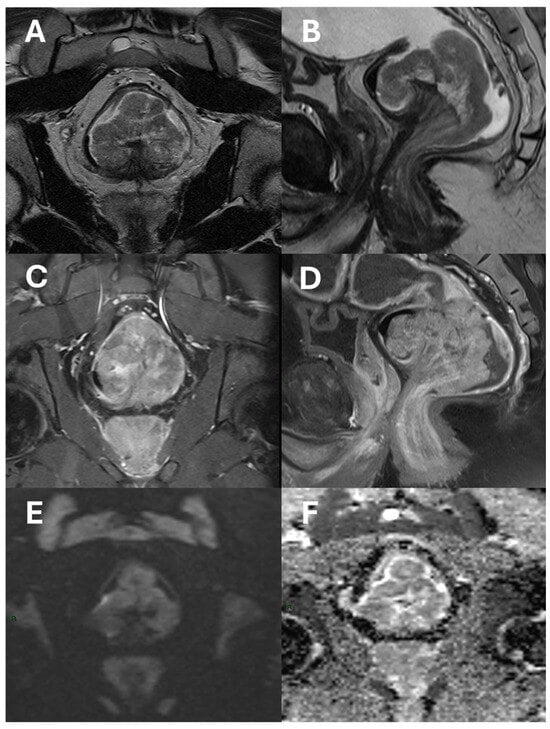

- Complexities of sphincter involvement: Our analysis revealed that sphincter involvement is strongly associated with heightened postoperative complications. This correlation, while not reaching traditional levels of statistical significance, suggests a complexity in surgical approaches when the sphincter is affected. It highlights the need for careful surgical planning and possibly more conservative approaches to preserve sphincter function and reduce complications. The significance of these findings emphasizes the importance of preoperative imaging reviews to better prepare for the challenges that may arise during and after surgery. There remains ambiguity regarding the management of low rectal cancers that affect the anal sphincter complex and the precise delineation, determining their classification as T4b [35]. The Society of Abdominal Radiology’s Colorectal and Anal Cancer Disease-Focused Panel recommends detailed description of anal involvement, specifying the location and length of sphincter muscle affected. This includes identifying involvement of the internal anal sphincter (IAS), intersphincteric space (ISS), or external anal sphincter (EAS) [36]. ESGAR aligns with this detailed approach, advising in detail the involvement of IAS, ISS, and EAS, along with specifying whether the tumor affects the proximal, middle, or lower third of the sphincter complex, and observing any pelvic floor involvement [10]. Providing comprehensive information about sphincter involvement plays a crucial role in the case-by-case decision-making process for patient management, aligning with multidisciplinary team recommendations.